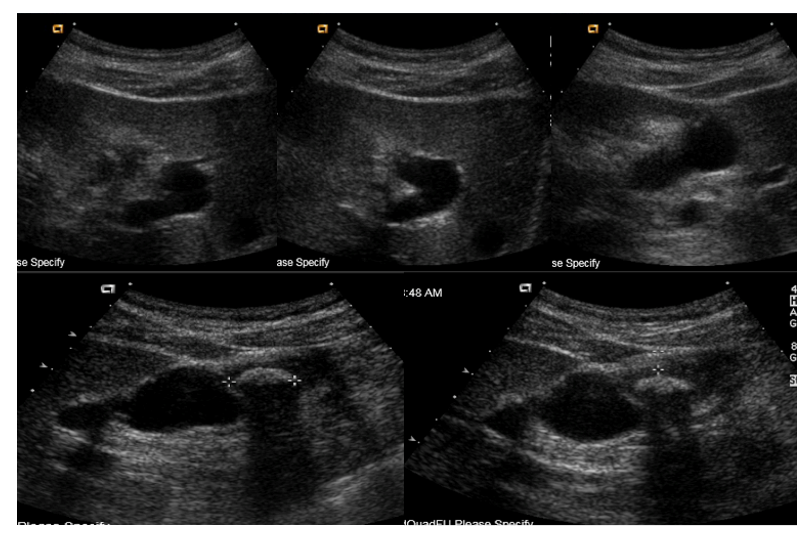

The patient is a 32-year-old Asian male who presented as an outpatient for evaluation of repeated epigastric and RUQ abdominal discomfort. The patient had no significant past medical or surgical history. Original imaging from several years prior showed a small stone in the gallbladder and he had been having intermittent abdominal pain for 2 years. Work-up of the symptoms at presentation included a RUQ ultrasound that revealed a 1.9cm calcified stone in the fundus of the gallbladder, causing localized wall thickening, and a 3mm channel that was believed to be the common bile duct. The remainder of the exam was insignificant for any other pathology in the visualized hepato-pancreatico-biliary system (Figure 1). The patient was scheduled for elective laparoscopic cholecystectomy given the significant increase in size of the gallstone and with the diagnosis of symptomatic cholelithiasis. The patient initially underwent the conventional 4-port cholecystectomy without any complication. After careful dissection in the area of the gallbladder neck, Calot’s Triangle was exposed, the critical view of safety was obtained, and what was thought to be the cystic duct was identified. Clips were placed proximal to the gallbladder neck and further distal along the cystic duct. The cystic artery was similarly clipped and both isolated structures were divided between the clips. The gallbladder was then dissected off of the liver bed without any complication until transection of the tissues around the scarred and fibrosed fundus to completely remove the gallbladder revealed a bile leak from a 4 to 5mm duct-like structure in this area. Given the leak, a clip was temporarily placed on the structure and the gall bladder was removed to allow for further examination of the anatomy and to perform an intraoperative laparoscopic cholangiogram. The clips were removed from the remnant cystic duct stump and the cholangiogram catheter was placed into the cystic duct. When contrast was injected into the duct, it went directly into the duodenum. The cholangiogram was then repeated after withdrawing the catheter to be certain that the tip was not too deep within the common bile duct. The results were the same and no proximal reflux was seen into a common bile duct even after morphine was given to contract the sphincter of Oddi. At this time, with unclear anatomy, the procedure was converted from a laparoscopic to open case in order to properly explore the porta hepatis via a right subcostal Kocher incision. The portal vein and hepatic artery were identified with no visualized common bile duct. A biliary probe was used on the proximal and distal stumps from the transected ductal structures with the proximal stump reaching the left and right intrahepatic ducts and the distal duct tracing directly into the duodenum. A biliary catheter was then inserted into the proximal duct to perform an intra-operative cholangiogram, which showed a duct stump 5 millimeters below the bifurcation of the right and left intra-hepatic ducts and a normal intra-hepatic biliary tree. This indicated that the most likely anatomy was a hepaticocystic duct secondary to agenesis of the common bile duct. The distance between the proximal and distal stump measured approximately 3cm. A retrocolic, Roux-en-Y hepaticojejunostomy was performed to repair the transected proximal hepatic duct. The patient remained stable throughout the entirety of the case and was managed on the surgical floor post-operatively. The patient recovered well, was able to tolerate a regular diet, and was discharged to home with normal liver function. On subsequent outpatient follow-up, the patient was fully recovered from the surgery and returned to his daily activities. He continues to be well four years post-operatively.